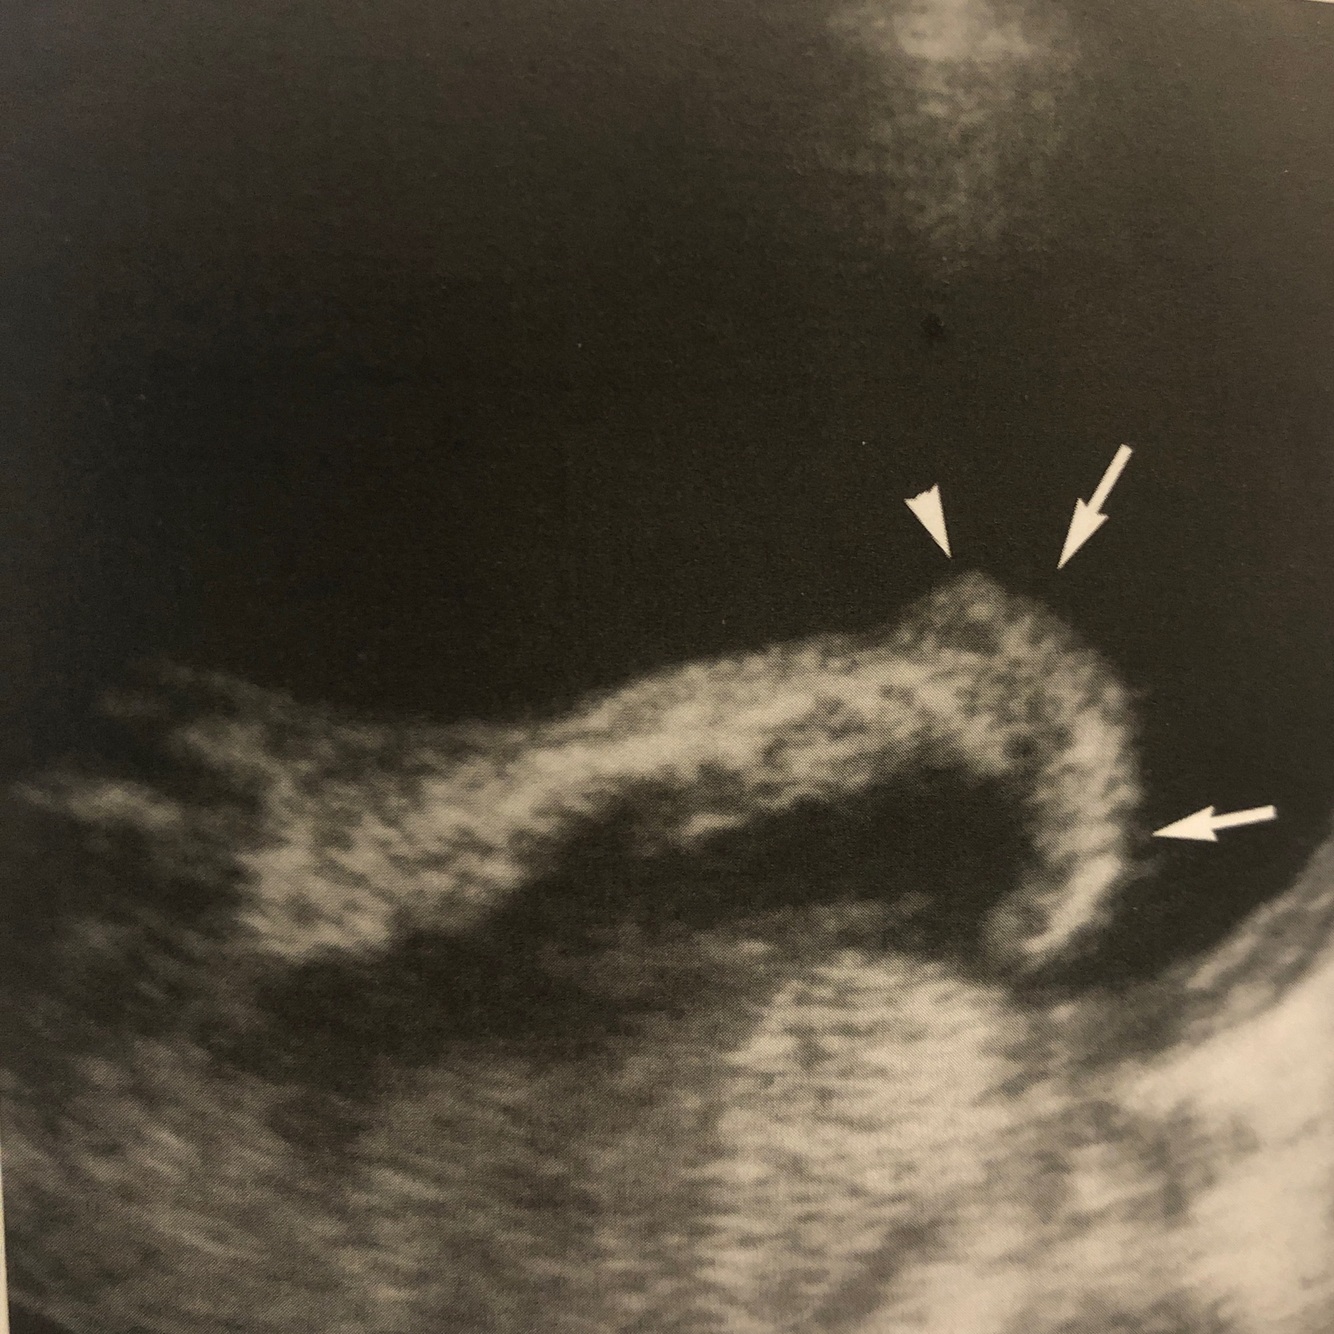

Q

What abnormality is this? What is it associated with?

A

Rocker bottom foot. Trisomy 18